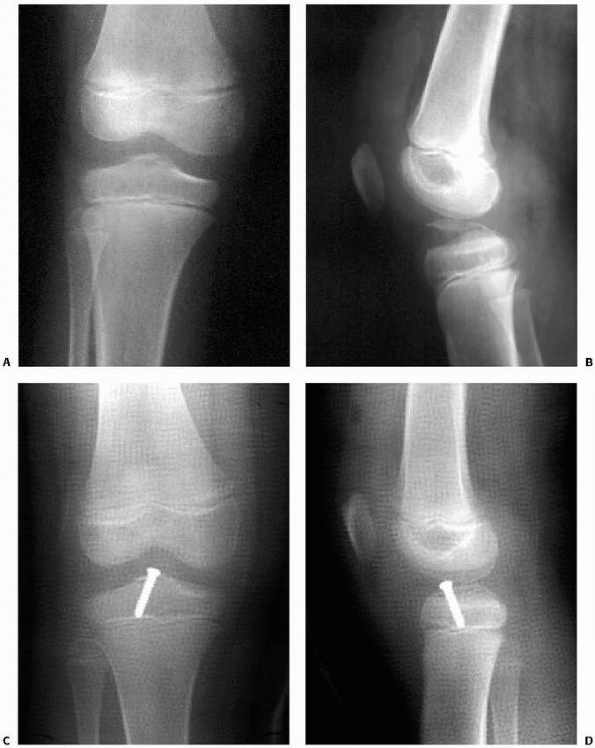

FIGURE 24-9 Arthroscopic reduction and cannulated screw internal fixation of a displaced tibial spine fracture. A. Elevation of the tibial eminence fragment. B. Débridement of the fracture bed. C. Reduction of the tibial eminence. D. Drilling over the cannulated screw guidewire. E. Cannulated screw fixation.

FIGURE 24-10

Type III tibial spine fracture in an 11-year-old male child treated with arthroscopic reduction and 3.5-mm cannulated screw fixation. Preoperative anteroposterior (A) and lateral (B) radiographs. Postoperative anteroposterior (C) and lateral (D) radiographs. |